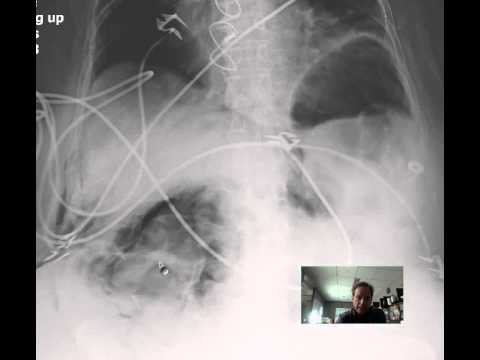

Rigler triad

Free Air Riglers Sign Discussion by RADIOLOGIST

The classic Rigler's triad of gallstone ileus